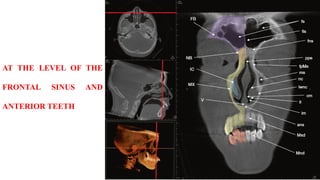

AT THE LEVEL OF THE

FRONTAL SINUS AND

ANTERIOR TEETH